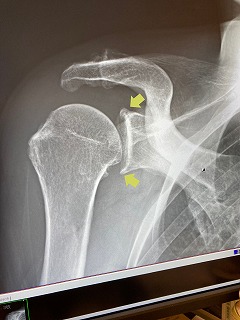

5月末、東HSYのパワーチュービーに巻かれて、右肩の亜脱臼、再び病院通い